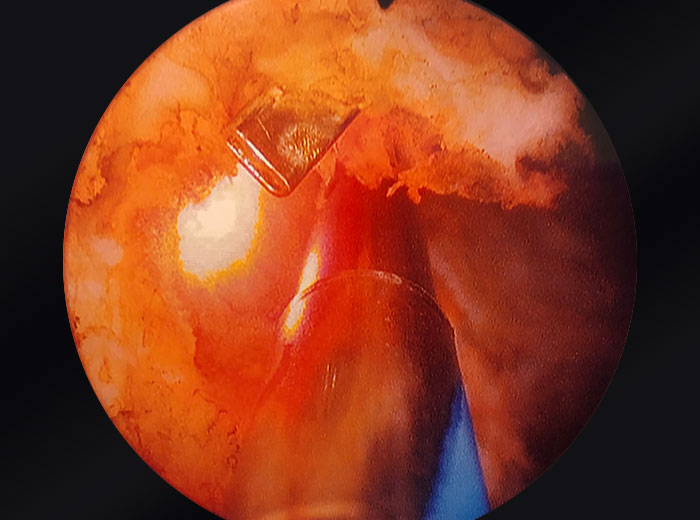

UroLift clips embedded in prostatic tissue

Images provided courtesy of Dr. Ricardo Gonzalez.

OR camera zoomed into prostate.

Tissue extracted from a Urolift procedure.